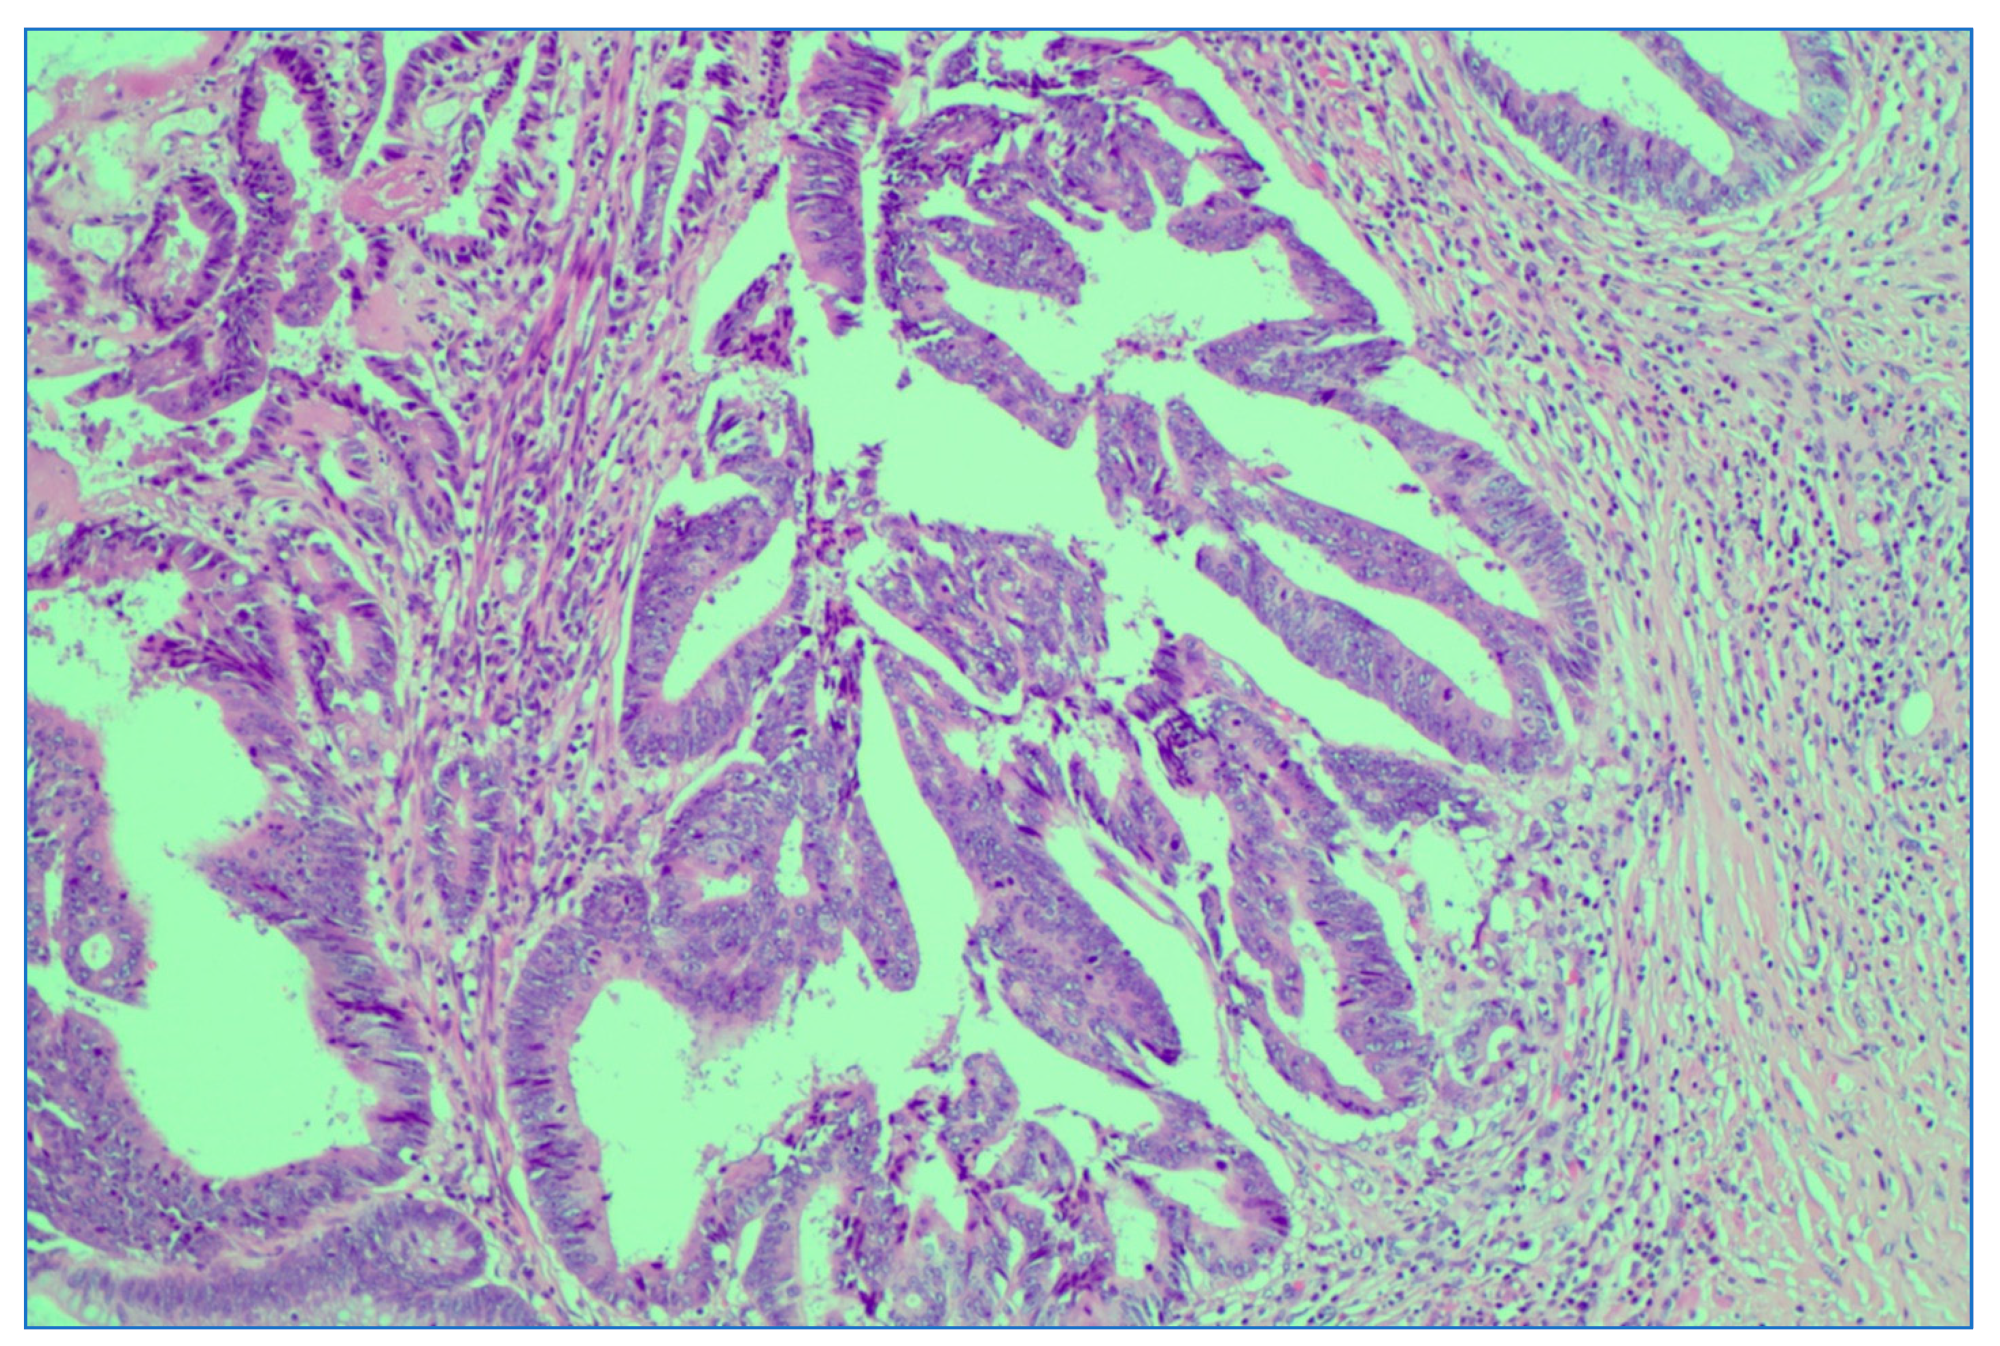

We analyzed the correlation between adjuvant chemotherapy treatment and histopathology bulletin results by using the Pearson correlation coefficient and applying the two-tailed significance t-test. The correlation between adjuvant chemotherapy and a pathological T staging greater than 2 (y)pT > 2 (Figure 6) and between adjuvant chemotherapy and a positive pathological N staging (y)pN > 0 was tested. Other risk factors from the histopathology report that were taken into account were the presence of lymphovascular invasion LVI+ (Figure 7), the presence of perineural invasion PNI+ (Figure 8), positive resection margins Postop+, or a histopathological grade greater than 1 Grade > 1.

Figure 7. Depiction of extramural lymphovascular invasion; carcinomatous emboli of rectal adenocarcinoma. HE stain × 20 magnification.